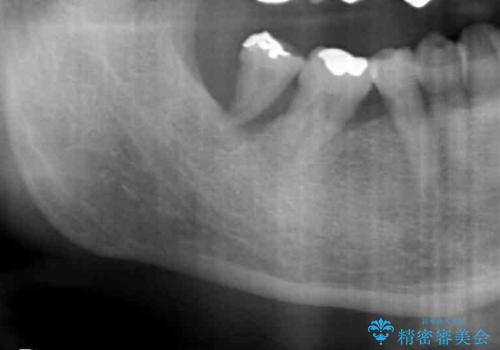

- 右下の親知らずが咬むと痛いとのことでした。

親知らずを抜いて、倒れこんでいる手前の歯を矯正治療で移動させ、ブリッジにしました。

矯正治療をしなければ、倒れこんでいる影響で手前の奥歯も含めて歯周病で悪化してしまうため、しっかり起こして治療をしました。